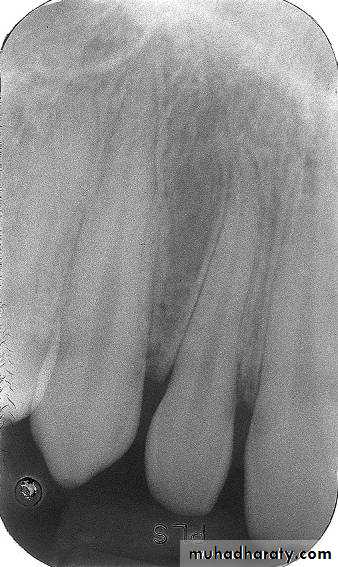

Periapical Examination

Main Indications:Detection of apical lesions.

Assessment of the periodontal status.

After trauma to the teeth and associated alveolar bone.

Assessment of the unerupted teeth.

Assessment of root morphology before extractions.

During endodontics.

Preoperative assessment and postoperative appraisal of apical surgery.

Evaluation of implants postoperatively.

There are two basic techniques for obtaining periapical radiographs:

Bisecting angle technique.Paralleling technique.